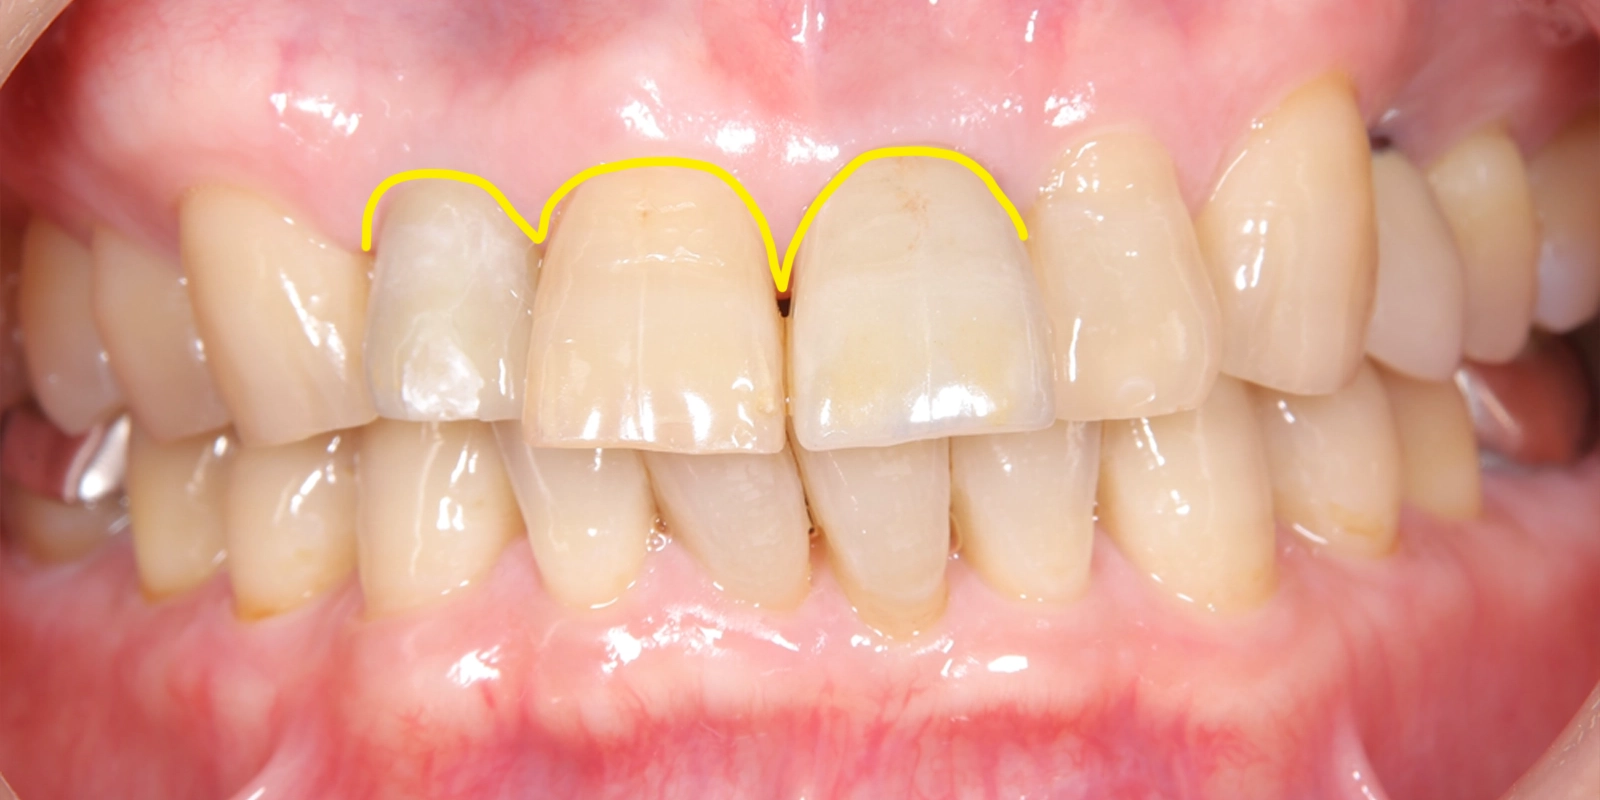

治療前の口腔内写真を確認すると、上顎前歯部には変色した大きな被せ物が複数装着されており、歯肉の広い範囲にわたって赤みと腫れが認められました。慢性的な炎症が長期間にわたって続いていた状態と考えられました。

治療前の写真では、上顎前歯部の歯肉に広範囲にわたる赤みが認められます。

歯肉が腫れた状態が続いていたことで、歯と歯肉の境目のラインも乱れており、前歯全体として整った印象とは言いにくい状態でした。

治療後の写真と比較すると、歯肉の赤みが落ち着き、引き締まった状態になっていることがわかります。歯肉の境目のラインや色調も整い、前歯部として自然な見た目に近づいています。

この黄色線がスキャロップ

治療後は隣の歯と光沢が調和した

矢印の中央の歯の色調と

左右のそれぞれの被せ物の色調を揃えた